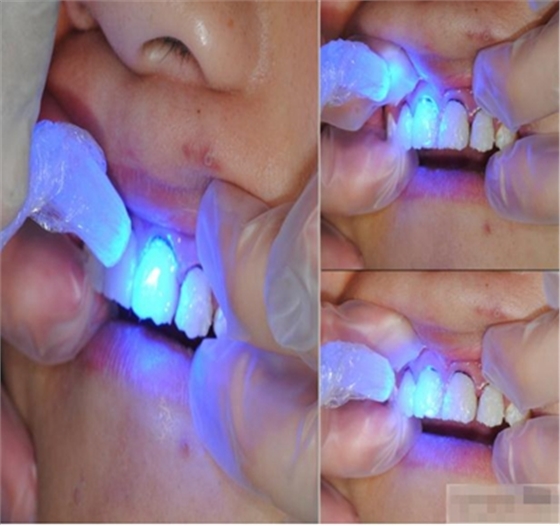

紙尖拭干

光照強(qiáng)度要達(dá)到800-1000毫瓦。鹵素?zé)舻拇┩噶σ劝l(fā)光二極管強(qiáng)。粘結(jié)嵌體時(shí)要用鹵素?zé)?。常?guī)應(yīng)用發(fā)光二極管燈更加方便。

【纖維刷拋光】

脂拋光中應(yīng)注意:樹(shù)脂拋光放到24H后為最佳,因?yàn)榇藭r(shí)收縮應(yīng)力最為平衡,特別是在固化后10min內(nèi)應(yīng)避免對(duì)樹(shù)脂修復(fù)體進(jìn)行外力加載,包括打磨拋光及冷熱張力等,因?yàn)榇似陂g收縮應(yīng)力變化明顯,拋光時(shí)的機(jī)械應(yīng)力會(huì)使釉質(zhì)層形成裂隙。

【充填完成】

1、樹(shù)脂貼面平齊牙齦邊緣是最佳設(shè)計(jì),或者使用齦上邊緣 。

2、釉質(zhì)邊緣要用橡皮輪拋光。拋光可以去除懸釉。這樣經(jīng)過(guò)車針打磨過(guò)的釉質(zhì)表面會(huì)更加均一,形成良好的邊緣封閉。

3、纖維樁通常深入到根管的1/2至2/3處。因?yàn)樽罴训恼辰有Чl(fā)生于根管的冠1/3和中1/3。由于根1/3的牙本質(zhì)小管往往不能充分敞開(kāi),此區(qū)域幾乎沒(méi)有粘接作用發(fā)生,所以,根管纖維樁放置的深度無(wú)需超過(guò)根中1/3。

4、修整纖維樁按所需長(zhǎng)度裁截纖維樁 在有水條件下 用切割砂片或車針截取纖維樁,切勿使用鉗子,剪刀或鑷子以免破壞樁的結(jié)構(gòu)。

5、為了提高樹(shù)脂的聚合轉(zhuǎn)化率,我們可以用防氧化劑,或者用甘油涂沫于樹(shù)脂的表面,或者修復(fù)體的間隙處,以利于樹(shù)脂的聚合。然后再進(jìn)行打磨拋光。